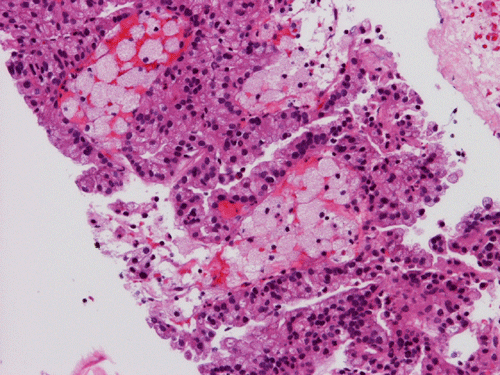

On FNA with Pap stain, clusters of cells with a papillary structure are present (Panel A). A delicate fibrovascular core can be seen at the center (arrow in Panel B). In higher magnification, two population of cells are present. While one of the population appears as solid sheets of polygonal epithelial cells with increased nuclear cytoplasmic ratio and distinct cell border (arrow head in Panel C), there are also many cells with distinctly foamy cytoplasm, lower nuclear cytoplasmic ratio and bland nuclei, and indistinct cell border (arrow head in Panel C). The foamy cells are most consistent with foamy macrophages. A distinct nucleoli is present in the epithelial cells (Panel D). The papillary morphology is well demonstrated in the cell block (Panel E, F, and G). Characteristically, the papillary structures are formed by a central core of foamy macrophages and covered by a epithelial cells. The epithelial cells but not the foamy macrophages are immunoreactive for CD10, AMACR, and CK7 (Panel H, I, and J).

Histologically, the proportion of papillary growth can vary. While papillary growth can be the dominant pattern in some tumor, tumors composed of predominantly solid growth areas can be seen. The papillary growth has fine, delicate fibrovascular cores. Foamy macrophages are usually abundant and they are usually wonderful diagnostic suggestions. However, it should be noticed that areas that lack foamy macrophages can occur. This is particularly important when the specimen is small such as FNA specimens. The tumor cells fall into two major cytologic types. Type 1 tumors cells vary from small cells with inconspicuous pale cytoplasm and small, uniform, spherical nuclei with small or invisible nucleoli. Type 2 tumor cells are larger cells with abundant eosinophilic cytoplasm and large, spherical nuclei, prominent nucleoli and pseudostratified arrangement. Mixed pattern within the same tumor is not uncommon. 1, 2, 4, 5